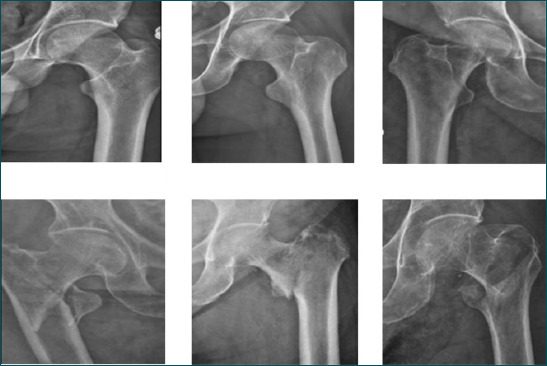

Methods: The study was conducted on a total of 598 plain pelvic X-ray images, including 296 patients with femoral neck fractures and 302 individuals without femoral neck fractures. Initially, transfer learning was applied using pre-trained deep learning models: VGG-16, ResNet-50, and MobileNetv2.

背景:股骨颈骨折是一个严重的健康问题,尤其是在老年人中。本研究的目的是利用深度学习和机器学习算法从骨盆x线平片诊断和分类股骨颈骨折,并比较这些方法的性能。方法:对598张骨盆x线平片进行研究,其中股骨颈骨折患者296例,非股骨颈骨折患者302例。最初,迁移学习应用于预训练的深度学习模型:VGG-16、ResNet-50和MobileNetv2。结果:预训练的VGG-16网络在股骨颈骨折检测和分类方面的性能略优于ResNet-50和MobileNetV2。采用VGG-16模型,准确率95.6%,灵敏度95.5%,特异性93.3%,精密度95.7%,F1评分95.5%,Cohen’s kappa为0.91,受试者工作特征(ROC)曲线为0.99。随后,使用常见的机器学习算法对VGG-16的卷积层提取的特征进行分类。其中,k近邻(k-NN)算法优于其他算法,比VGG-16模型的准确率高出1%。结论:采用深度学习和机器学习方法对股骨颈骨折进行检测和分类,取得了成功的结果。该模型可通过多中心研究进一步完善。所提出的模型对于在急诊科工作的医生和那些在评估骨盆平片方面没有足够经验的医生可能特别有用。